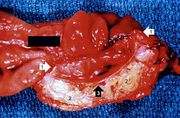

| 04:15, 19 August 2013 | IPLab3ChronicPepticUlcer2.jpg (file) | 61 KB | Seung Park | This is a gross photograph of the ulcer after it has been transected. The edge of the mucosa (1) is better appreciated in this image. Note the thick, fatty tissue (2) which makes up the base of this ulcer (3). | 1 | |